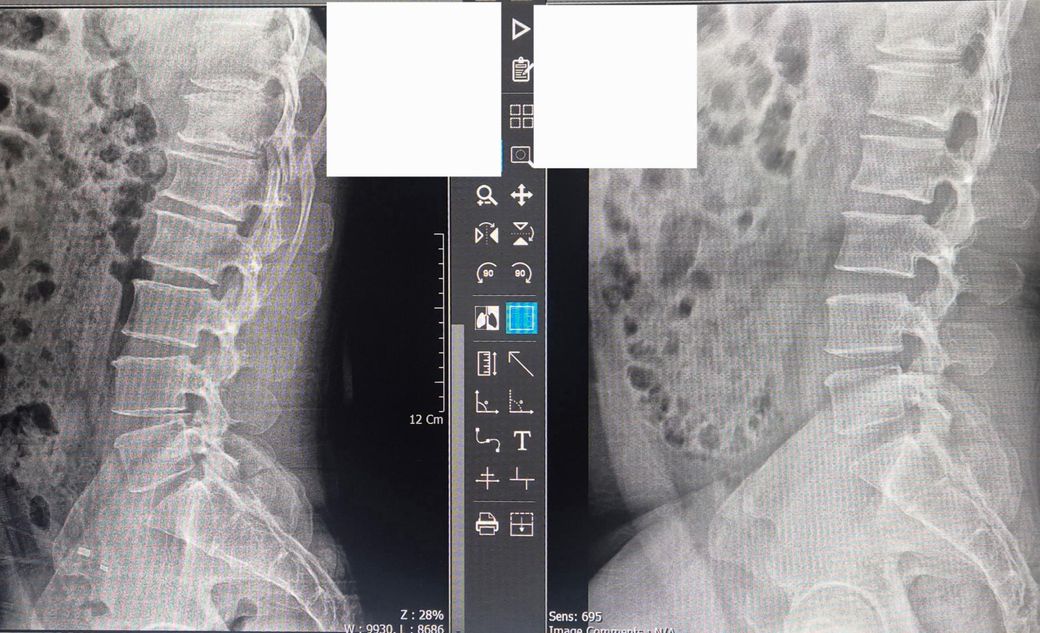

좌측으 사진은 2025년 사진이고 우측은 2021년 사진입니다

딱 4년 간격의 사진인데 허리가 많이 안좋아 진건가요?

오히려 4년 그 이전 2018년 2019년에 요추염좌도 있었고 디스크도 터져서 수핵이 흘러나온적도 있었는데 그때 이후 사진은(우측사진) 양호한 편이라고 하는데 왜 그 이후 별일 없었던 4년 시절동안 이렇게 변해버렸을까요.. 그 사이동안 허리가 직접 아팠던적은 없었거든요..

사진상 4년 사이 헐의 퇴행성 변화나 척추 불안정, 골극 등이 진행된 것으로 입니다. 과거 디스크 수핵 탈출 후 회복 되었어도 시간이 지나면서 자연스러운 퇴행성 변화가 발생할 수 있습니다.

우선 엑스레이 사진상으론 4년전보단 척추의 디스크 공간이 좁아진것으로 보여집니다.

다만 4년동안 큰 통증이 없었더라도 장시간 앉아있으면서 허리의 무리가 갔거나, 우리 인체는 퇴행성이 진행되면서 퇴행성으로 척추의 디스크 공간이 좁아 질 수 있습니다.